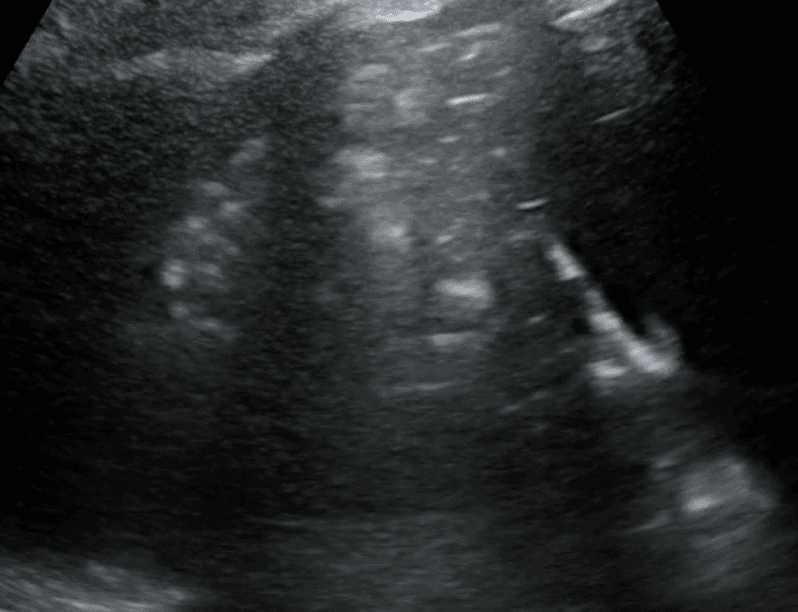

Consolidated lung appears dark due to its increased density and in some instances, may take on a similar texture to the liver. This is often referred to as “hepatization of the lung.”

Air bronchograms are air-filled bronchi that remain patent within the surrounding consolidated lung, They appear as hyperechoic structures within the hypoechoic consolidation. They may resemble multiple millimeter-long, lentil-shaped structures or branching tubular structures.

A shred sign represents the boundary between consolidated (abnormal) and aerated (normal) lung tissue. It appears as an irregular (shredded/fractal) line next to normal lung.